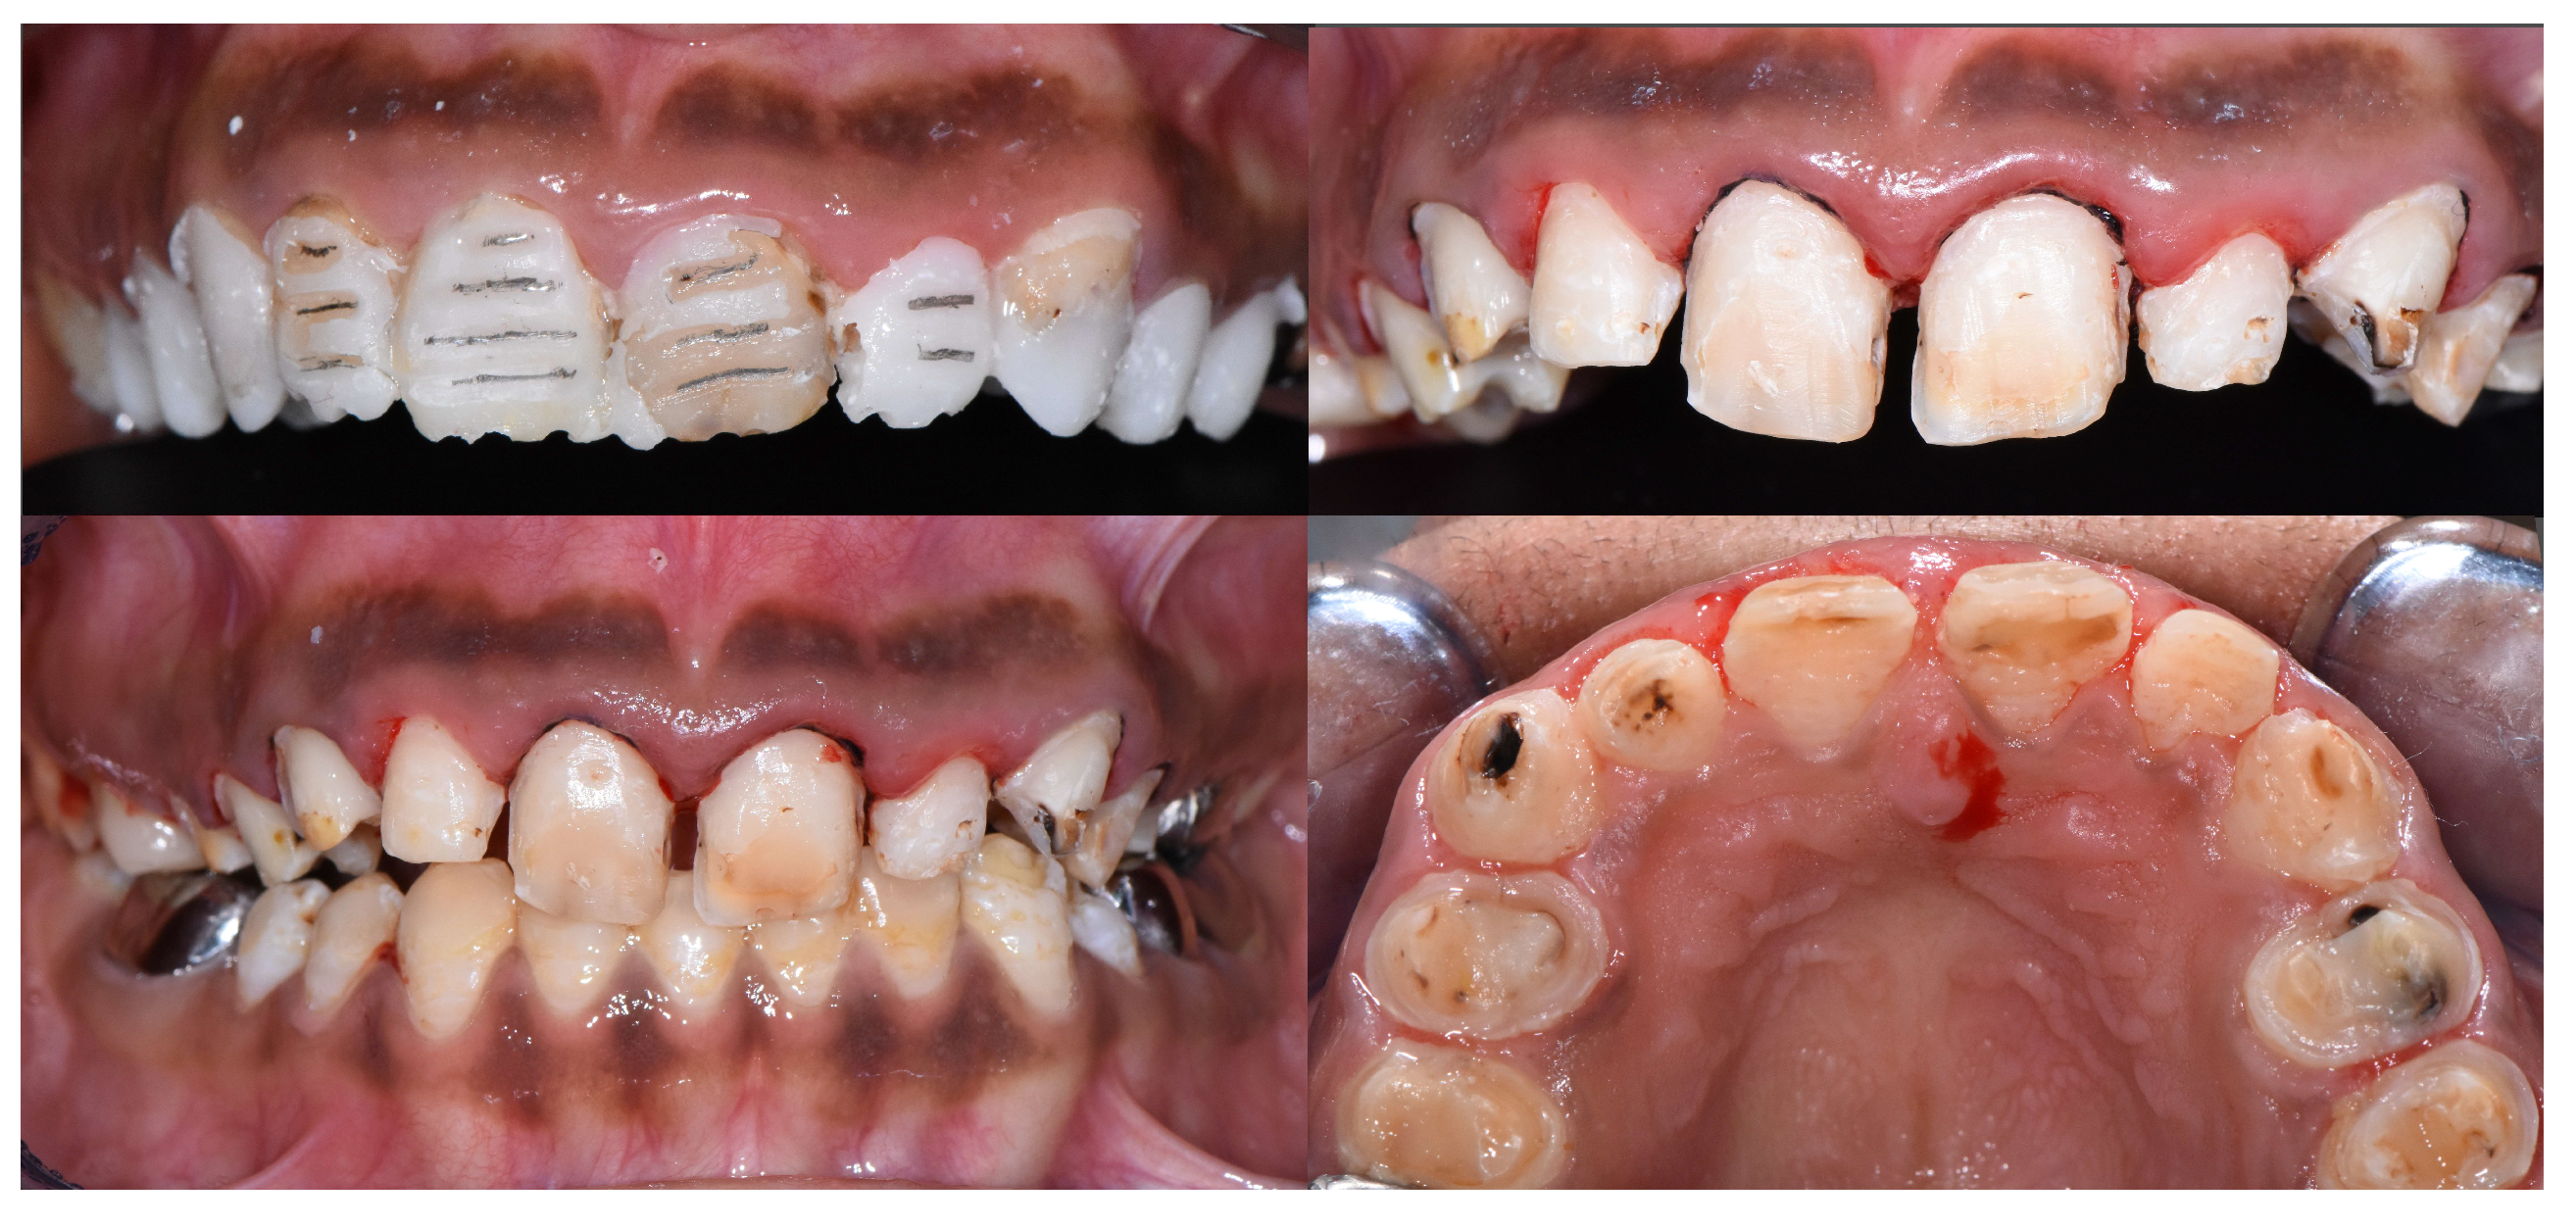

2.2. Clinical Examination

2.3. Radiographic Examinations